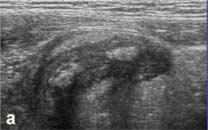

а, б - конгломерат лимфоузлов (исследование

в В-режиме и ДДС) в правой подвздошной области у ребенка

6 лет, перенесшего ОРВИ с абдоминальным синдромом 3 недели

назад. Лимфоузлы небольших размеров, преимущественно -

плоские, средней эхогенности. |

в, г - В-режим и ДДС выявляет конгломерат

лимфоузлов у 4-х летнего ребенка с абдоминальным болевым

синдромом на фоне ОРВИ (2-ые сутки заболевания). Лимфоузлы

крупные (до 24 мм), пониженной эхогенности, преимущественно

- округлой формы. |